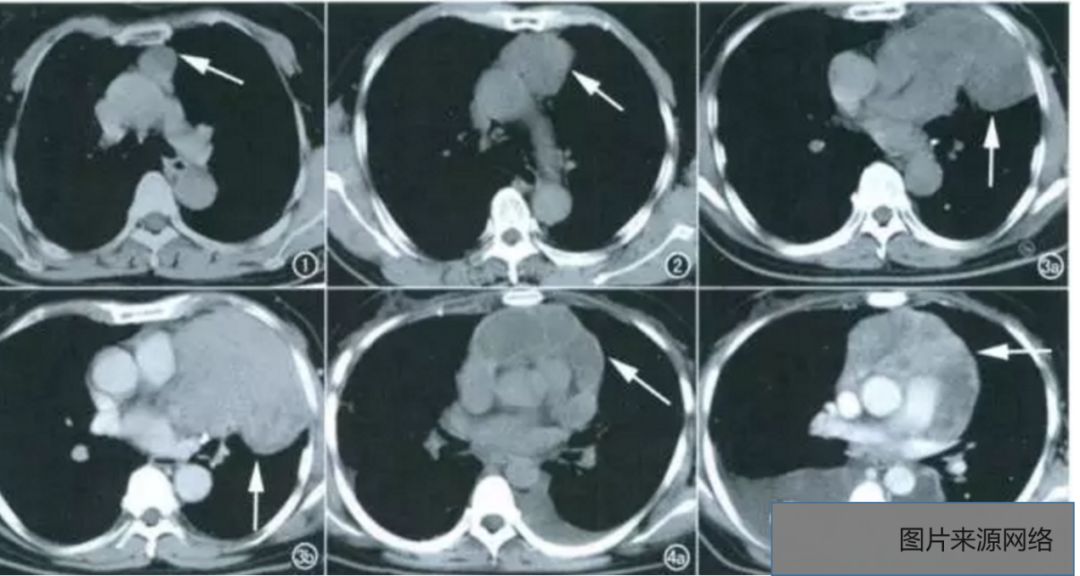

4.淋巴瘤

发生于淋巴结或节外淋巴组织的恶性肿瘤,分何杰金氏病(Hodgkin disease,又称霍奇金淋巴瘤)和非何杰金氏淋巴瘤(non-Hodgkin disease,又称非霍奇金淋巴瘤)。好发于前、中纵隔,多同时侵及多个淋巴结。

纵隔肺门多个淋巴结增大可融合成肿块,呈分叶状,向纵隔双侧突出,有时一侧明显,但很少为单侧。气管受压移位、变窄。可向肺内及胸膜、心包浸润,引起积液。中等强化。

淋巴瘤影像学表现